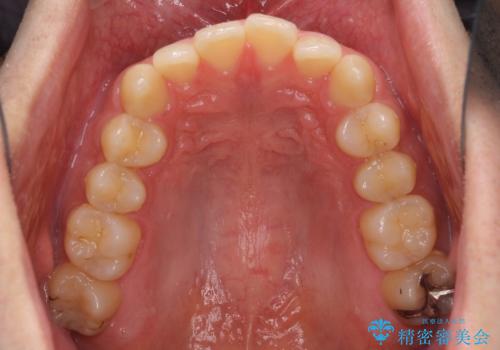

前歯の咬み合わせとデコボコを解消 インビザラインによる矯正治療

- 上下前歯のデコボコと深い咬み合わせを気にして来院された患者様です。

インビザラインによる上下歯列の拡大と、IPR(歯と歯の間を削る)にるスペースの獲得により、前歯のデコボコとディープバイトを改善することとしました。

もう少し下の前歯を整えたかったのですが、患者様の治療を早く終了させたいという希望により、細かい叢生を残しての終了となりました。